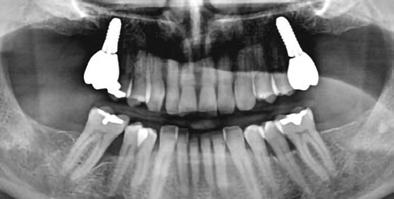

20–22. ábra: 2017-es, 2019-es és 2022-es panorámaröntgen-felvételek.

16. ábra: Klinikai kép az implantátumok körüli lágyszövetről a végleges pótlásátadás után. – 17. ábra: Klinikai kép az implantátumok körüli lágyszövetről egy évvel az átadást követően. – 18. ábra: Klinikai kép az implantátumok körüli lágyszövetről két évvel az átadást követően. – 19. ábra: Klinikai kép az implantátumok körüli lágyszövetről öt évvel az átadást követően.